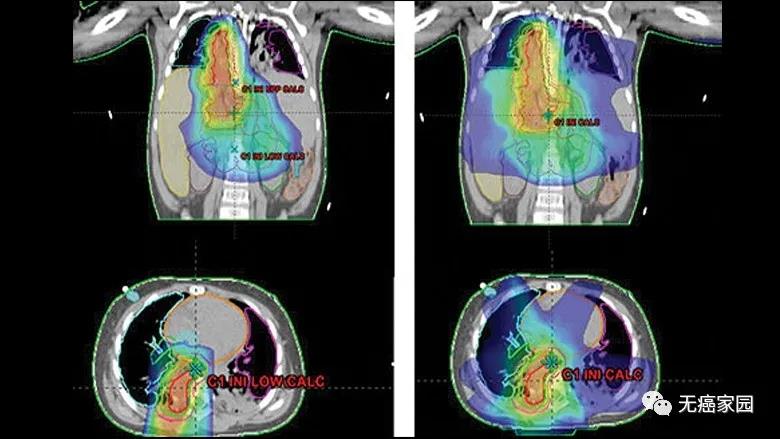

其中,原发性神经母细胞瘤通常起源于肾上腺,但可能累及副交感神经系统的其他解剖结构。位于肾上腺的神经母细胞瘤邻近肾、肝、胰腺及小肠;较为罕见的胸部神经母细胞瘤邻近肺和心脏。因此,既想照射剂量不影响身体的重要器官,又能获得有效的治疗可谓是难上加难。

有研究表明,儿童神经母细胞瘤使用质子治疗的最大效益在于减少脑部正常组织构造的损伤,进而降低长期伤害。质子治疗是一种比其他任何形式的放射治疗更准确,更精确地靶向肿瘤,同时保留健康组织,目前全球最先进的一种放疗技术。通过质子治疗,可以最大限度地避免靶标外部的绝大多数不必要的辐射。

与传统形式的辐射相比,质子束会到达肿瘤内部的精准位置而不是沿着光束离开人体的路径释放大部分辐射剂量。实际上,质子没有肿瘤之外的辐射“退出剂量”,这意味着质子停在肿瘤上,不会继续伤害身体的健康部位。

除此之外,有临床研究中的有一则典型案例,1例3岁的神经母细胞瘤患儿在使用质子治疗后,其对患者正常肝、肺和心脏的放射剂量比X射线治疗减少100倍!更重要的是,质子治疗不仅降低了患儿先前因化疗而增加的肺毒性风险,也降低了她的肝脏和肾脏毒性风险,让她在完成放疗后可以迅速接受所需的免疫治疗。后来,该患儿耐受放射线,无临床毒副作用,目前无病。